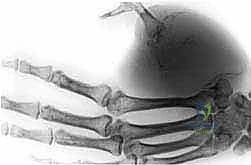

الطرف العلوي للإنسان ليس مجرد عظام وعضلات؛ بل هو أداة التفاعل الأساسية مع العالم المحيط. يتكون الطرف العلوي من شبكة شديدة التعقيد تشمل:

* العظام: عظمة العضد (Humerus)، وعظمتي الساعد (الكعبرة والزند)، وعظام الرسغ واليد.

* الأوعية الدموية: الشرايين والأوردة الرئيسية التي تغذي الطرف، والتي غالباً ما تتخذ الأورام الخبيثة منها مساراً للانتشار السريع.

* الأعصاب: الضفيرة العضدية (Brachial Plexus) والأعصاب الطرفية التي تتحكم في الحركة والإحساس.

عندما ينشأ ورم خبيث (مثل الساركوما) في هذه المنطقة، فإنه يميل إلى التغلغل بين هذه الأنسجة الحيوية. إذا أحاط الورم بالشرايين والأعصاب الرئيسية بشكل كامل، يصبح استئصال الورم مع الحفاظ على طرف يعمل بشكل وظيفي أمراً مستحيلاً طبياً، وهنا يبرز دور التدخل الجراحي الجذري كطوق نجاة.